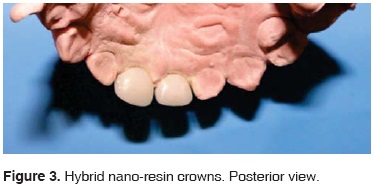

During the first visit, impressions were taken with irreversible hydrocolloid; and over the model teeth were carved with a 169 L bur, 1 mm were eroded at all sides, rounded borders without retention and shaping a cervical chamfer. The model was then sent to the laboratory in order to manufacture crowns, with shape and color specifications (Figures 2 and 3).